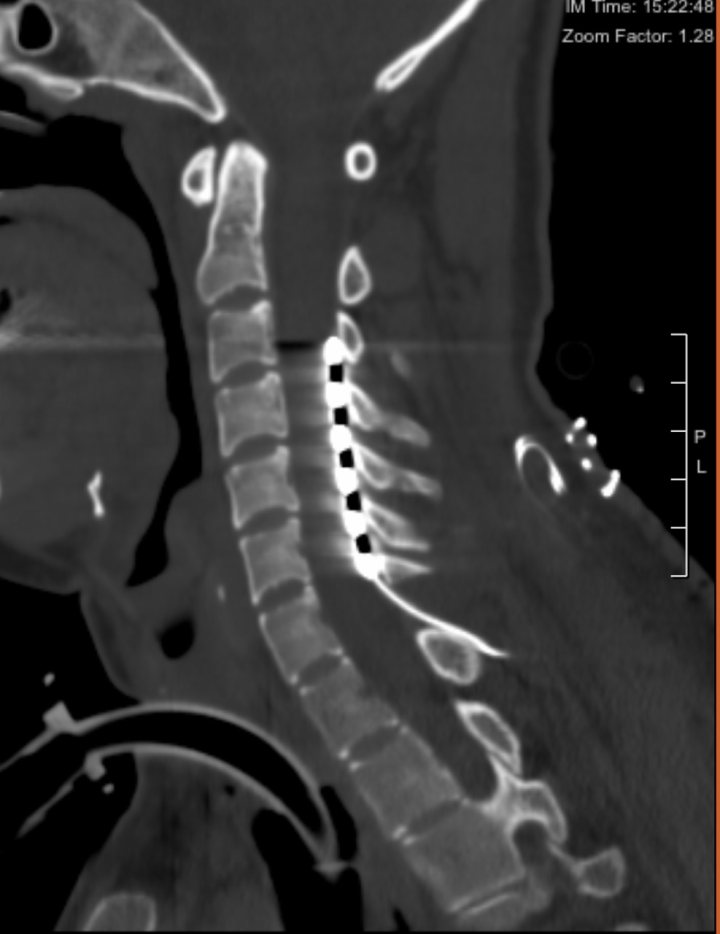

脊髓神经刺激器置入影像